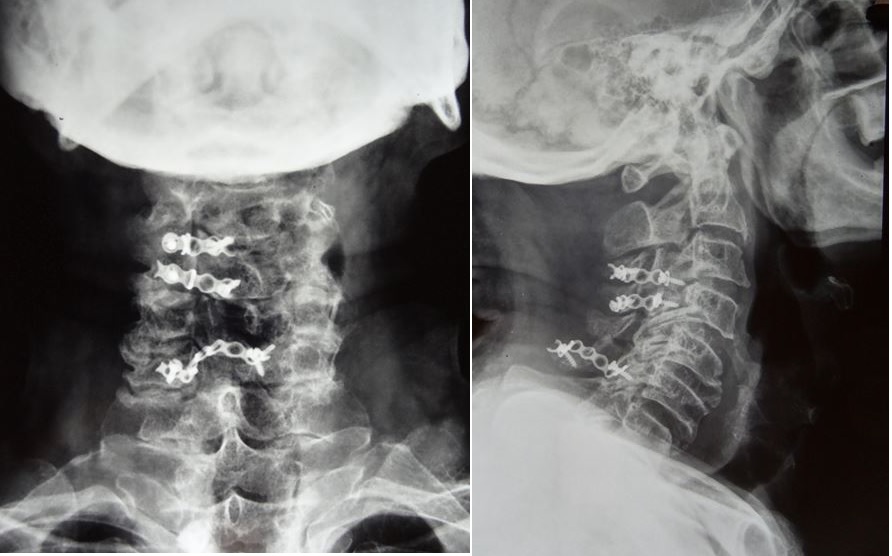

Basilar invagination, a rare condition in which the odontoid (part of neck bone) is abnormally higher inside the brain and compressing the uppermost part of spinal cord. This patient presented with spastic quadriparesis (difficulty in walking and hand work).

Operated him by a complex surgery called DCER and occipitocervical fixation uneventfully. Complete reduction of Basilar invagination achieved. Patient improved completely and mobilised the day after surgery.